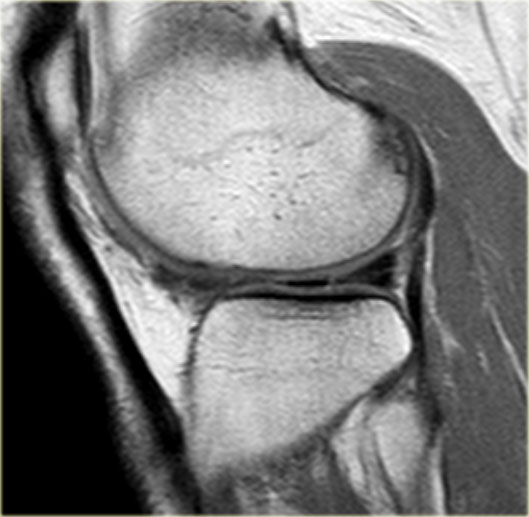

Hãy quan sát hình ảnh bên trái và cố gắng xác định vấn đề của sụn chêm này là gì.

Sau đó tiếp tục xem các hình ảnh liên tiếp tiếp theo của cùng bệnh nhân này.

Như bạn đã đoán được qua tiêu đề của đoạn này, đây là một trường hợp sụn chêm lật (flipped meniscus).

Sụn chêm lật là một dạng đặc biệt của rách dạng quai xô (bucket-handle tear).

Sụn chêm lật xảy ra khi mảnh vỡ của sừng sau bị lật ra phía trước, khiến sừng trước của sụn chêm có vẻ to hơn bình thường.

- Thân sụn chêm ngoài.

- Sừng sau quá nhỏ và sừng trước có vẻ to hơn với đường viền không đều.

- Thoạt nhìn có vẻ như có một đường rách dọc ở sừng trước, nhưng thực chất phần sau của cấu trúc này chính là phần lật của sừng sau bị rách.

Cấu trúc phía trước là sừng trước.

Cũng cần lưu ý tình trạng phù tủy xương khu trú và dấu ấn lõm sụn khớp. - Cấu trúc phía trước là sừng trước.

- Một số bất thường ở phần sau.

- Phần sau di chuyển về phía đuôi (caudal).

- Trong hố gian lồi cầu là điểm nối giữa mảnh di lệch và phần còn lại của sừng sau.